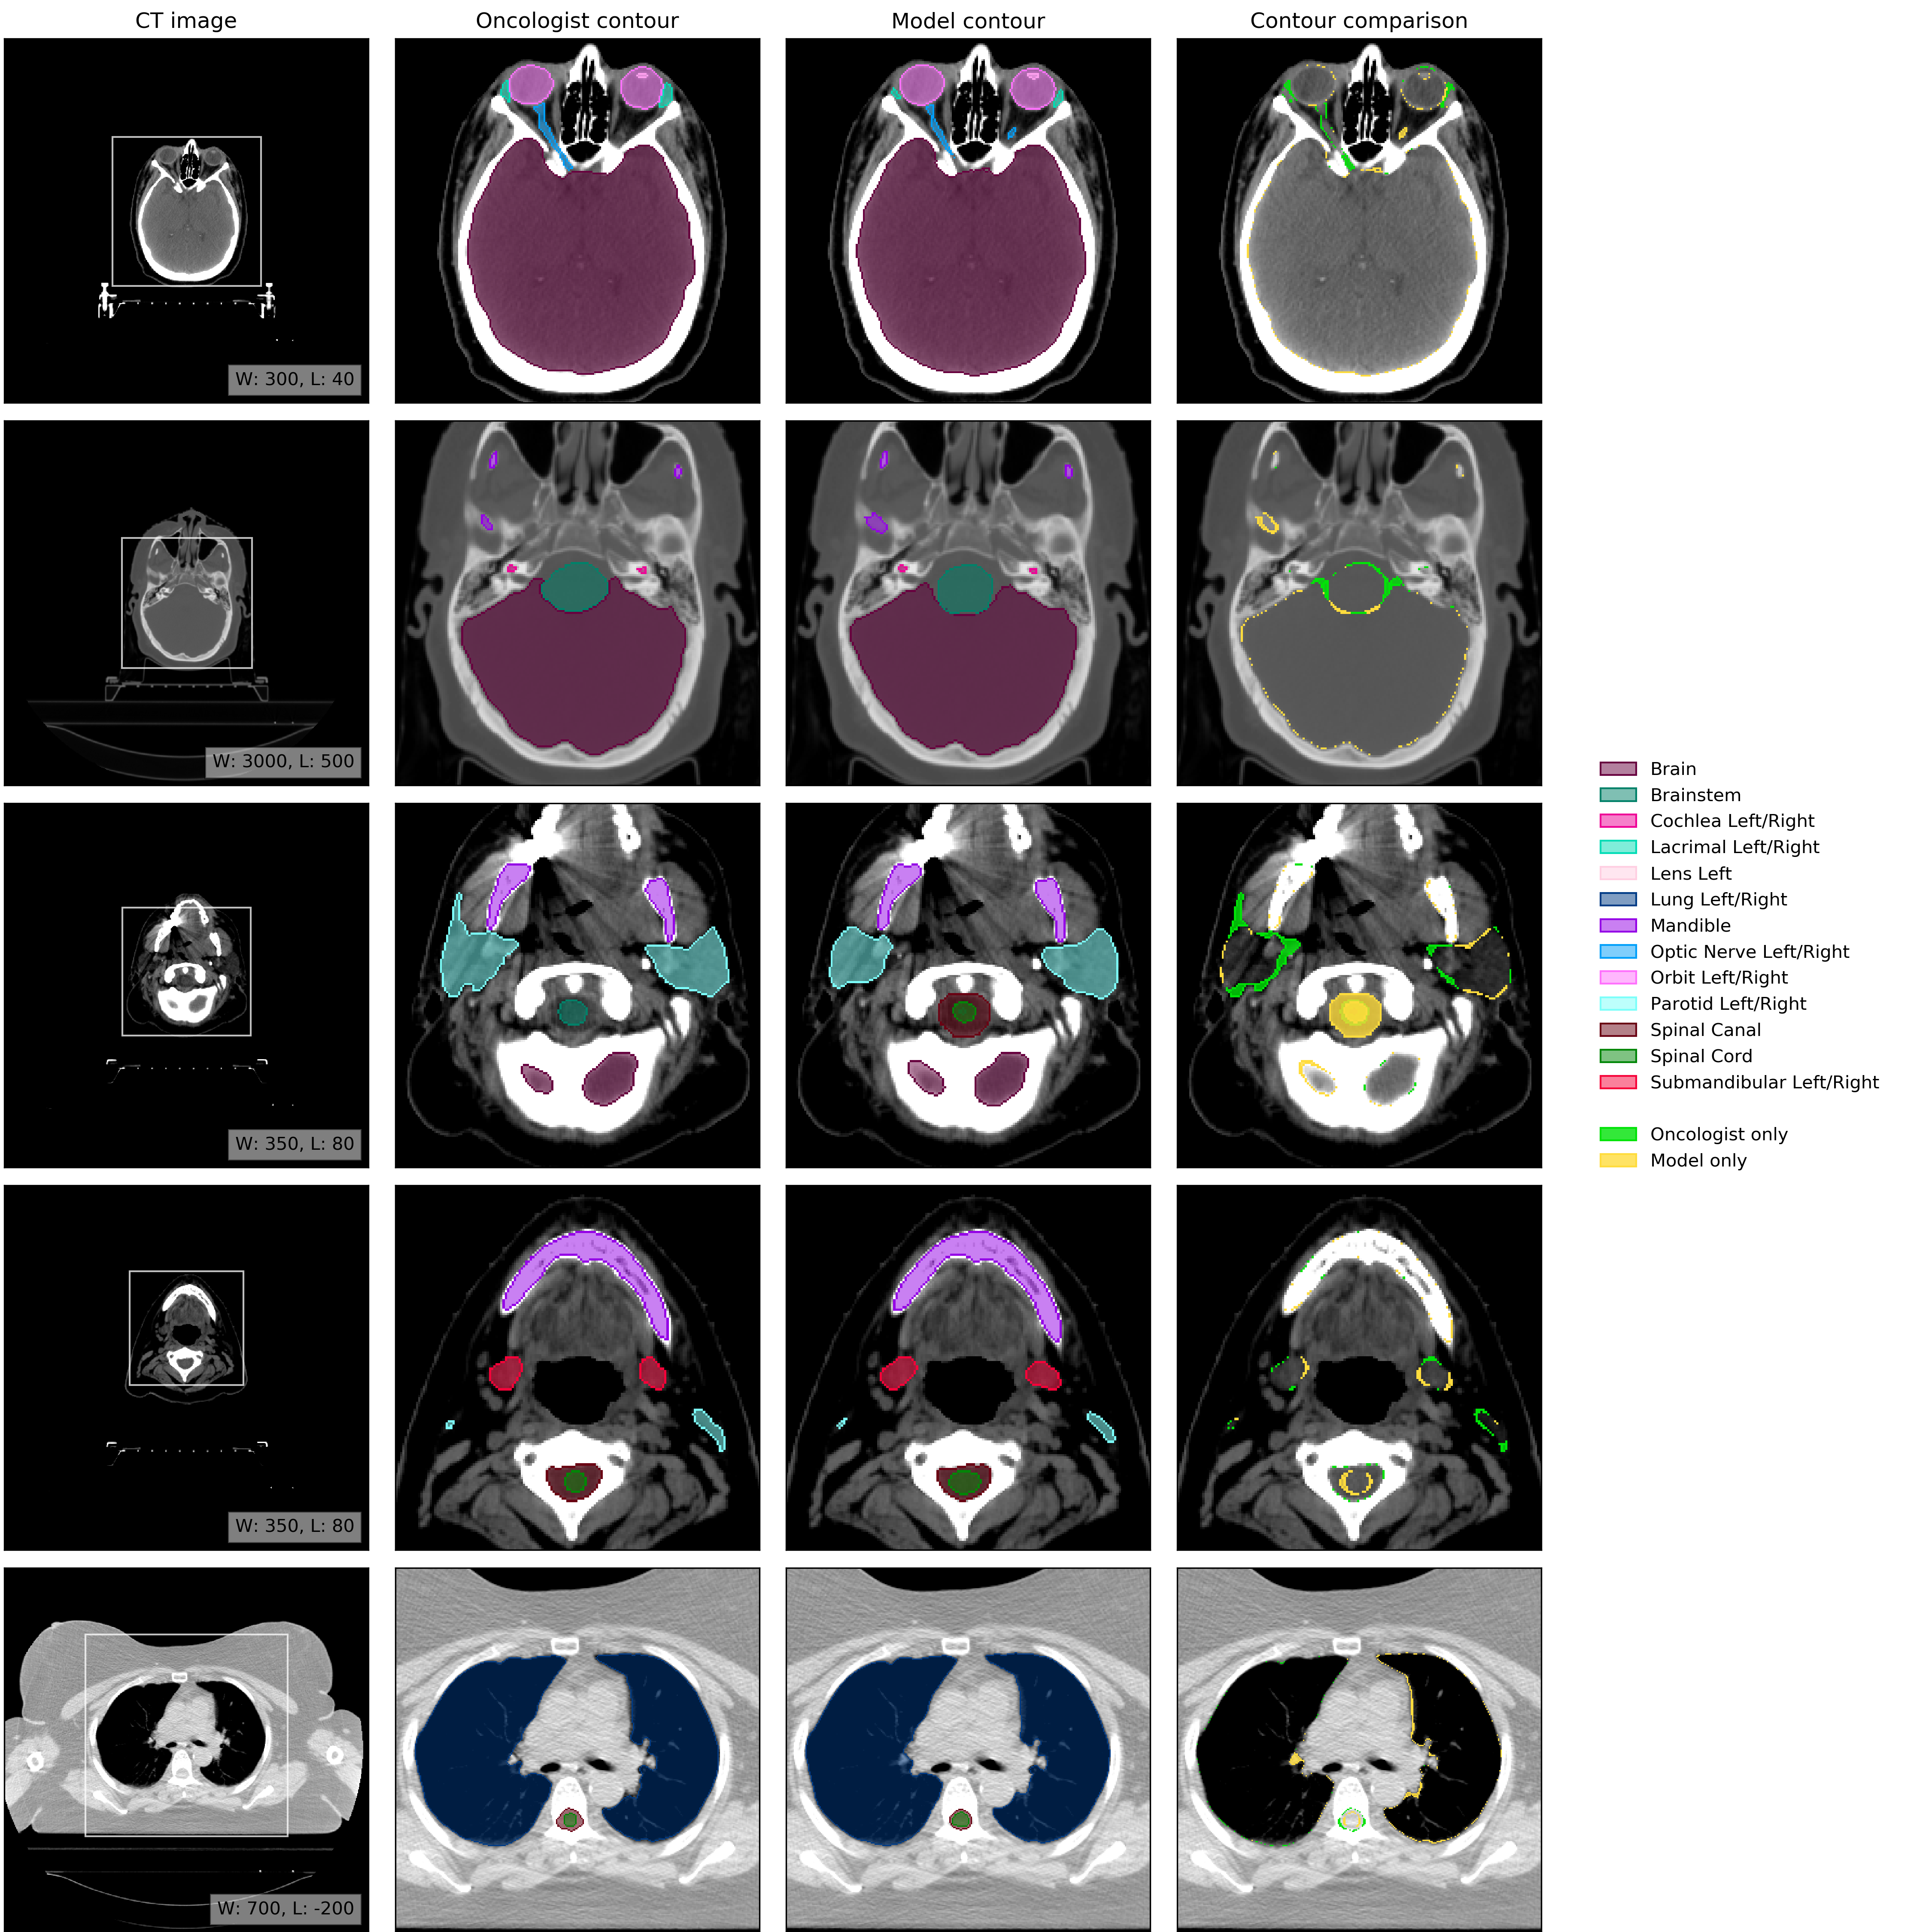

An example of model performance is shown in Fig. 2. We compare our performance (model vs oncologist) to radiographer performance (radiographer vs oncologist). For more information on dataset selection, inclusion and exclusion criteria for patients and OARs please refer to the Methods section.

Refer to caption

Figure 2: Example results. (CT image) Axial slices at five representative levels from the raw CT scan of a 55-59 year old male patient was selected from the UCLH dataset (patient UCLH-20) were selected to best demonstrate the OARs included in the work. The levels shown as 2D slices have been selected to demonstrate all 21 OARs included in this study. The window levelling has been adjusted for each to best display the anatomy present. (Oncologist contour) The ground truth segmentation, as defined by experienced radiographers and arbitrated by a head and neck specialist oncologist. (Model contour) Segmentations produced by our model. (Contour comparison) Contoured by Oncologist only (green region) or Model only (yellow region). Two further randomly selected UCLH set scans are shown in Fig. 12 and Fig. 13. Best viewed on a display.